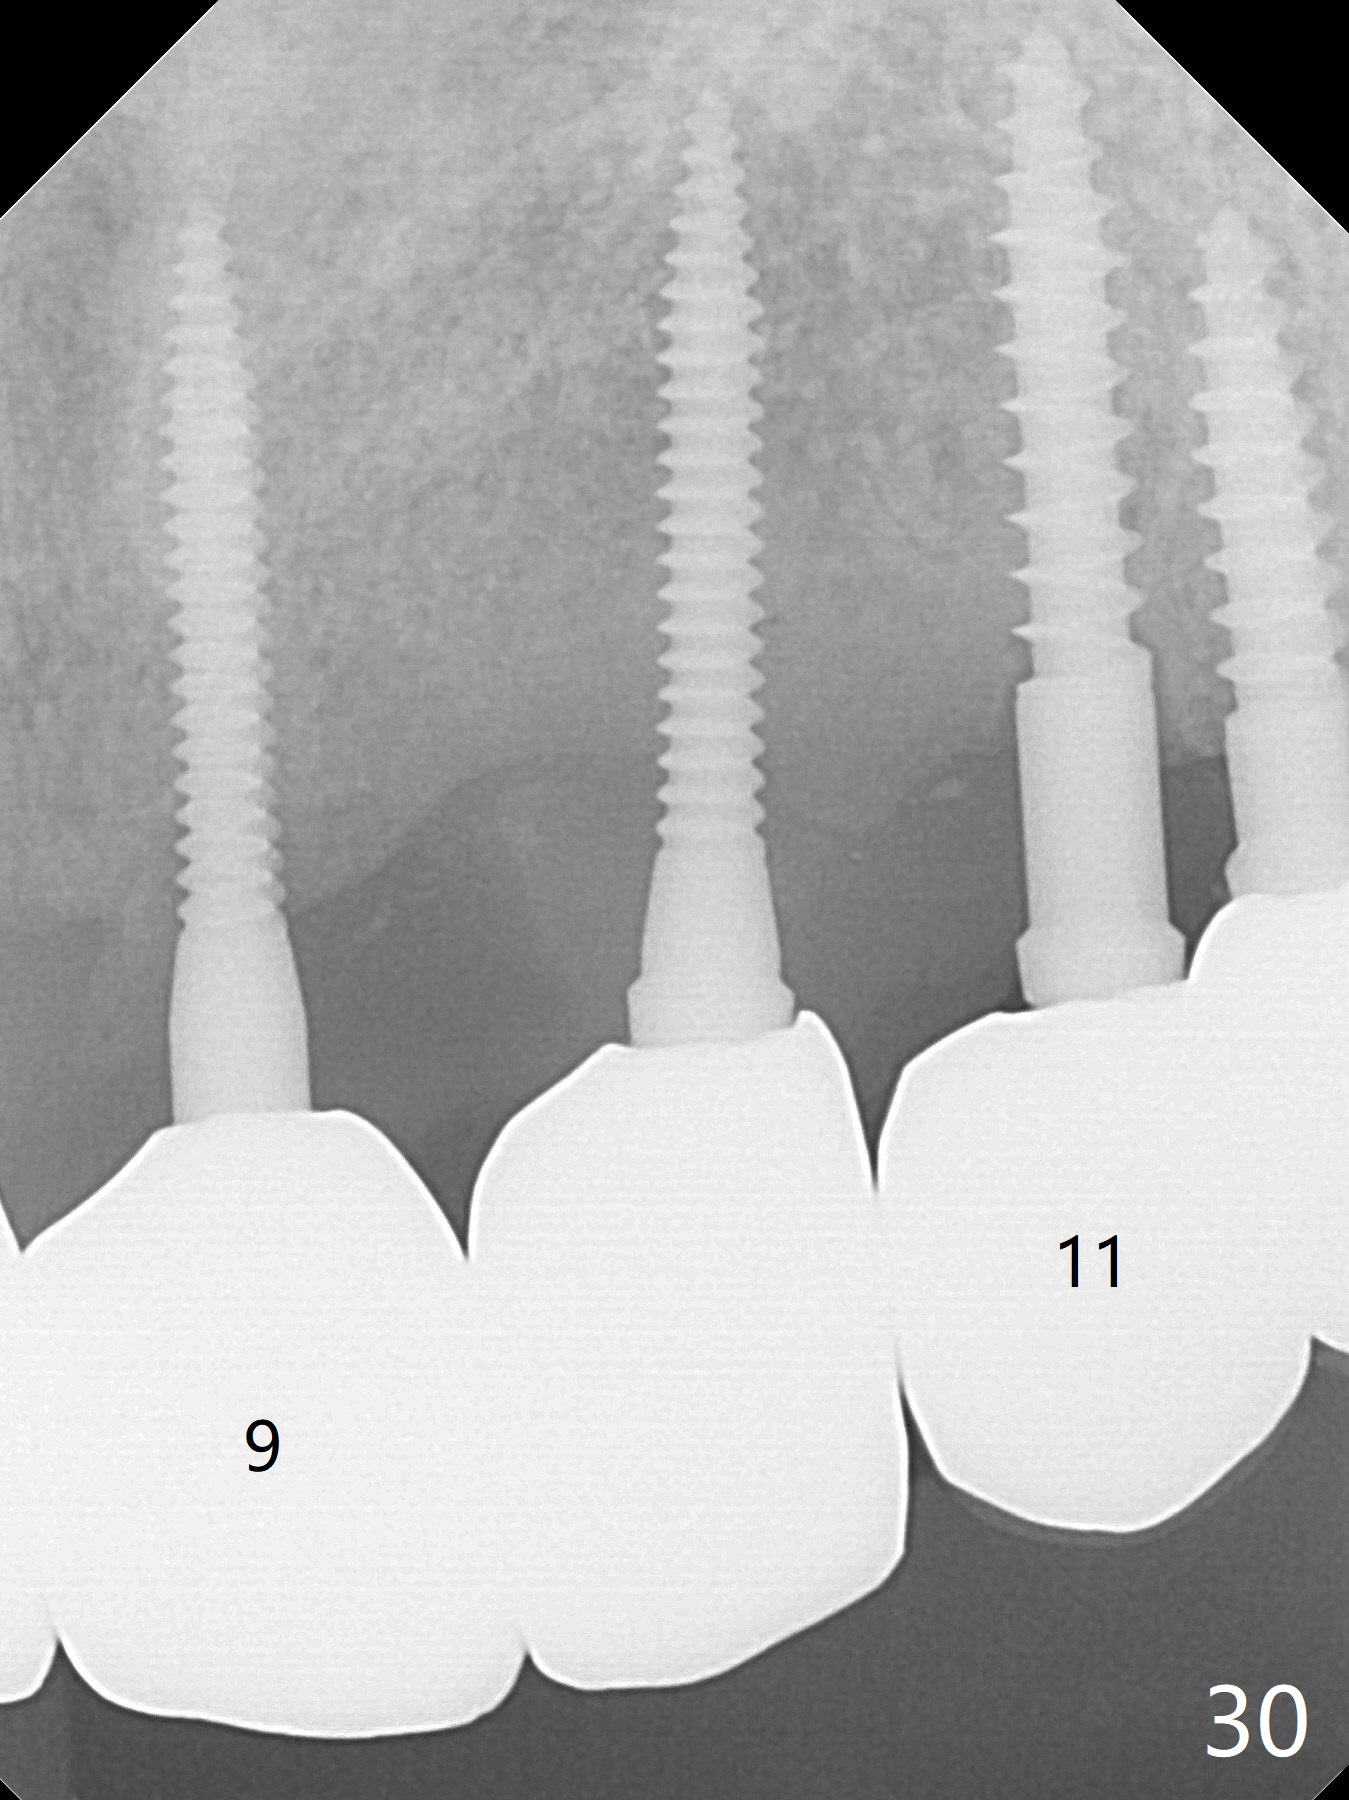

The gingiva remains healthy with use of water pik at #8-10 (4 months post cementation) and at #11-13 (immediately post cementation (1 year 2 months postop, Fig.27,28), while bone loss is minimal (Fig.29-31, although the crowns at #8 and 9 received trauma from child head immediately post cementation with tenderness for 1-2 months). The patient is pleased with convenience of the fixed restoration.